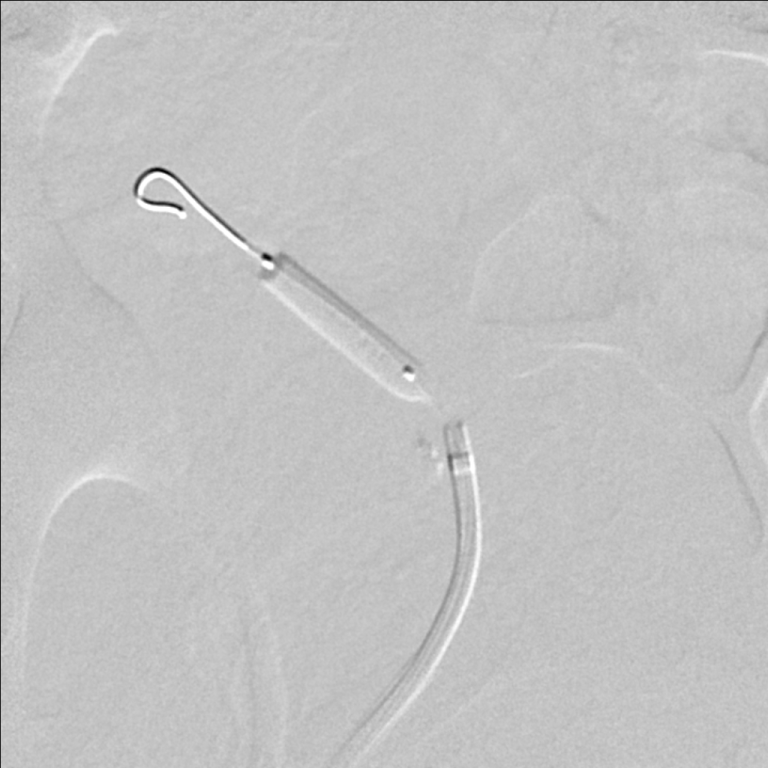

The patient was referred for renal angiography, which revealed a focal web-like stenosis in the mid portion of the transplanted renal artery (Figure 1). A Fractional Flow Reserve (FFR) wire was advanced through the stenosis and a 45 mmHg gradient was noted across the lesion. Subsequently, a 5 × 20 mm RX Viatrac 14 Plus balloon (Abbott Vascular, Inc., CA, US) was crossed and inflated to its nominal pressure (Figure 2). Post-angioplasty (Figure 3), the systolic gradient across the stenosis decreased to 25 mmHg. More aggressive dilatations were not performed because of the proximity of the stenosis to the bifurcation of the renal artery. A decrease in the blood pressure was noted in the recovery room and remained controlled without antihypertensive therapy in the subsequent visits.

Figure 1: Unselective iliac artery angiography, using a pigtail catheter, showing the transplanted renal artery stenosis in its mid portion. View Figure 1